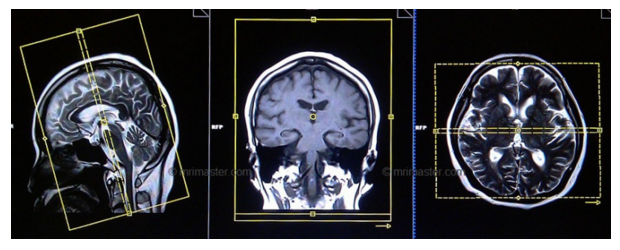

- Также Вы можете посмотреть, что должно получиться в результате - какое изображение считается качественным при исследовании конкретной зоны исследования с использованием определенной импульсной последовательности (напр. Ax T2 или Sag T1 при исследовании ГМ - Головного мозга). Для этого достаточно кликнуть на символ соответствующей импульсной последовательности внизу страницы: